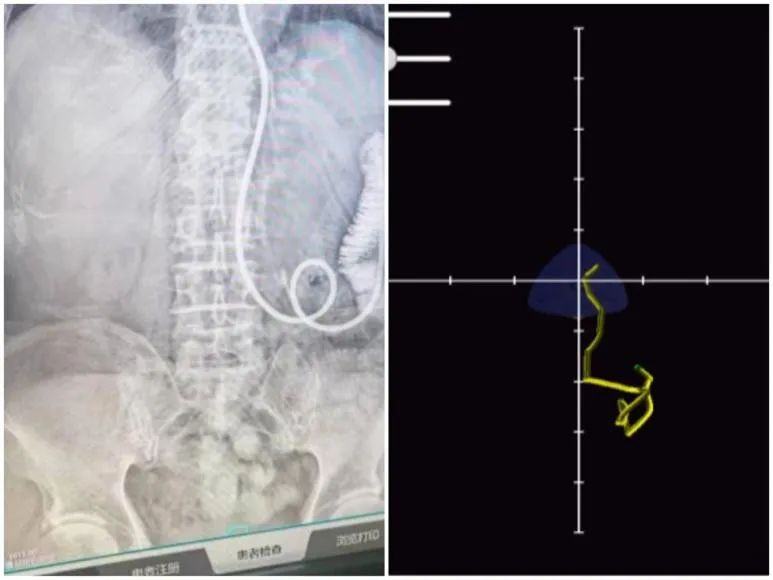

图为:X光检查下鼻肠管显像及磁导航下鼻肠管轨迹对比

78岁周爷爷,因胃恶性间质瘤根治术行全胃切除术,术中放置一根鼻肠营养管维持机体需要营养,术后三周鼻肠管堵塞后无法使用,周爷爷无法经口进食,影响机体恢复,需置鼻肠管维持身体的营养需求。但盲插法和胃镜引导下均容易造成吻合口损伤,重症医学科团队利用磁导航技术顺利通过两个吻合口到空肠,成功完成鼻肠管置管,再次开通营养通路。